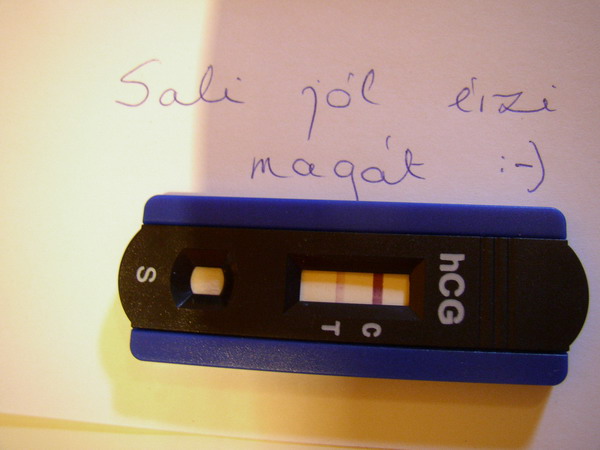

Pénteken két gyönyörű blasztocisztát kaptunk vissza. Azt mondta a biológus, hogy nagyon szépek, egységes a felületük és 50 órán belül be is fognak ágyazódni.